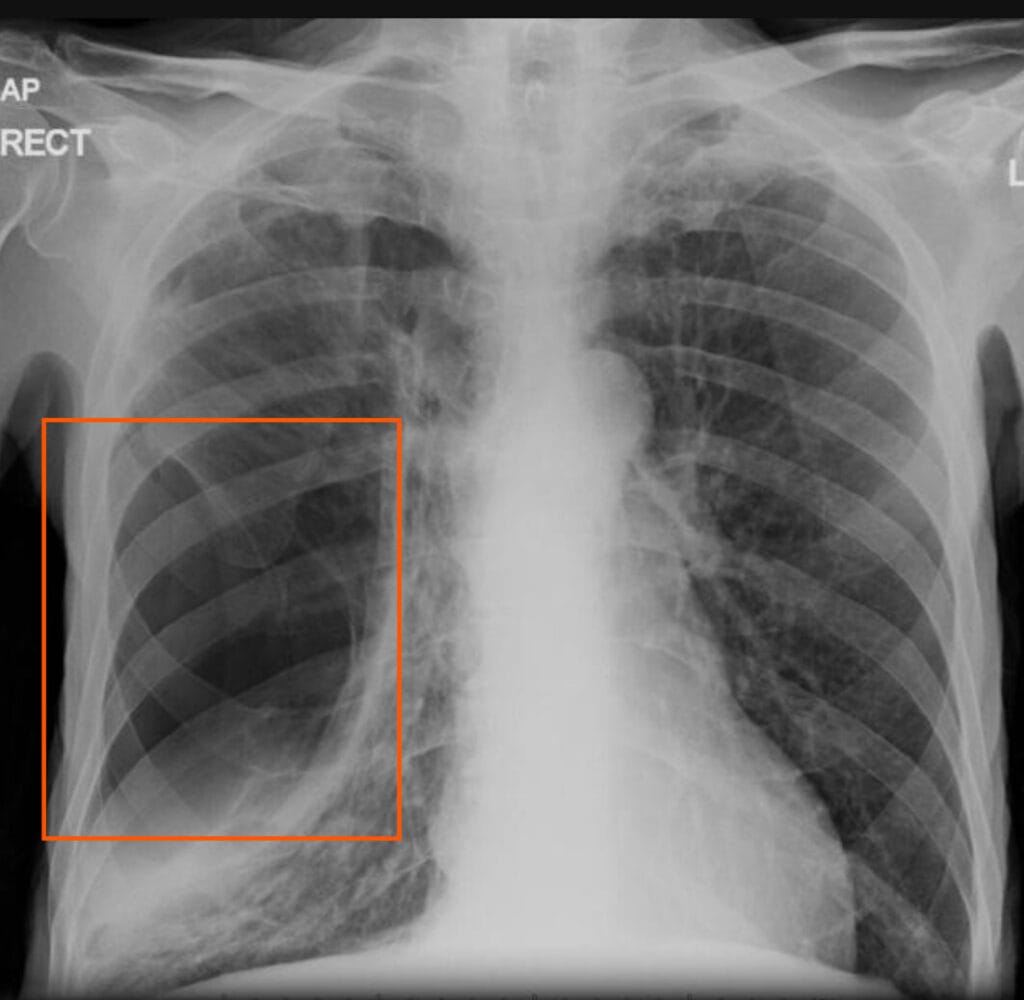

기흉(Pneumothorax)의 진단

흉부 X-ray와 CT를 이용하여 기흉의 범위 및 상태를 평가.

주로 영상 검사를 통해 진단되며, 흉부 X-ray와 CT가 주요 진단 도구로 사용됩니다. 기흉이 있는 경우 폐허탈, 늑막선(pleural line), 폐 내 공기 음영 소실 등의 특징적인 영상 소견이 관찰됩니다.

| 주요 검사 |

| 🔵흉부 X-ray: 폐 허탈, 늑막선(pleural line) 확인. |

흉부 X-ray 소견

기흉 진단의 1차적 검사로, 공기 음영과 폐 허탈 여부를 평가.

| 흉부 X-ray 소견 |

| 🔵 늑막선(pleural line): 공기와 허탈된 폐 조직 사이의 경계선이 관찰됨. |

| 🔵 폐 실질 음영 소실: 기흉 부위에는 폐 혈관 음영이 보이지 않음. |

| 🔵 폐 허탈: 폐가 수축되어 정상적인 부피보다 작아짐. |

| 🔵 긴장성 기흉의 경우: 종격동 편위, 횡격막 하강, 늑간근 견인 등이 동반됨. |

Ballinger J, Pneumothorax: inspiratory and expiratory films. Case study, Radiopaedia.org (Accessed on 23 Mar 2025) https://doi.org/10.53347/rID-23725

영상 소견상 특징

- Right Upper Lobe의 음영 소실

- Pleural line (Red arrow)

영상 소견상 특징

- Large lucent area with surrounding compressed Lung